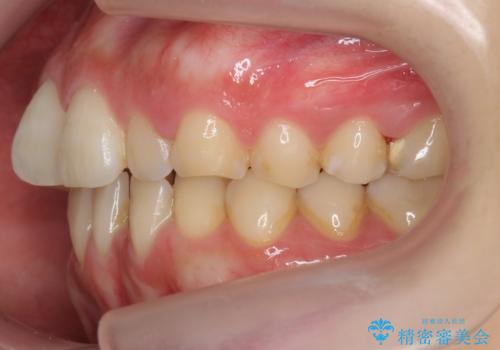

下の前歯が3本になるため、上下の正中は合わない仕上がりとなりますが、正中を合わせるには上下左右4本抜歯の上、ワイヤー矯正となってしまいます。

短期間できれいな歯並びになり、大変満足していただきました。